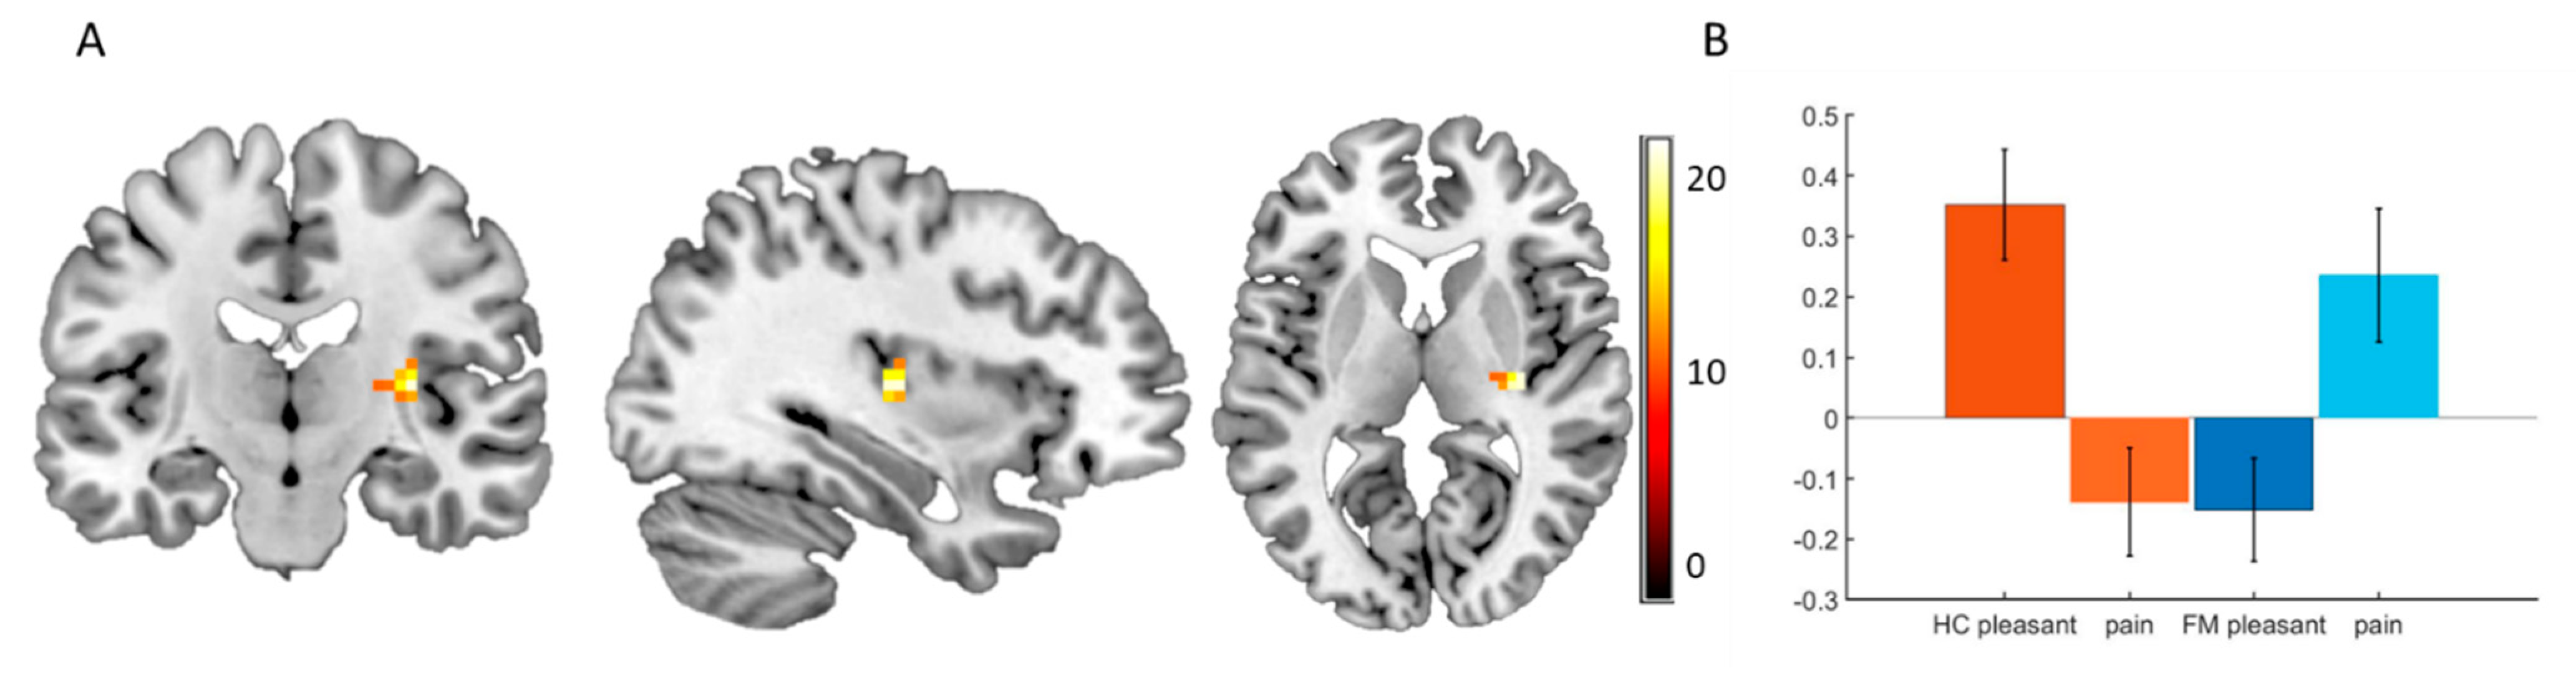

3.3. Functional Imaging

3.4. Voxel-Based Morphometry

4.2. Functional Imaging

4.3. VBM